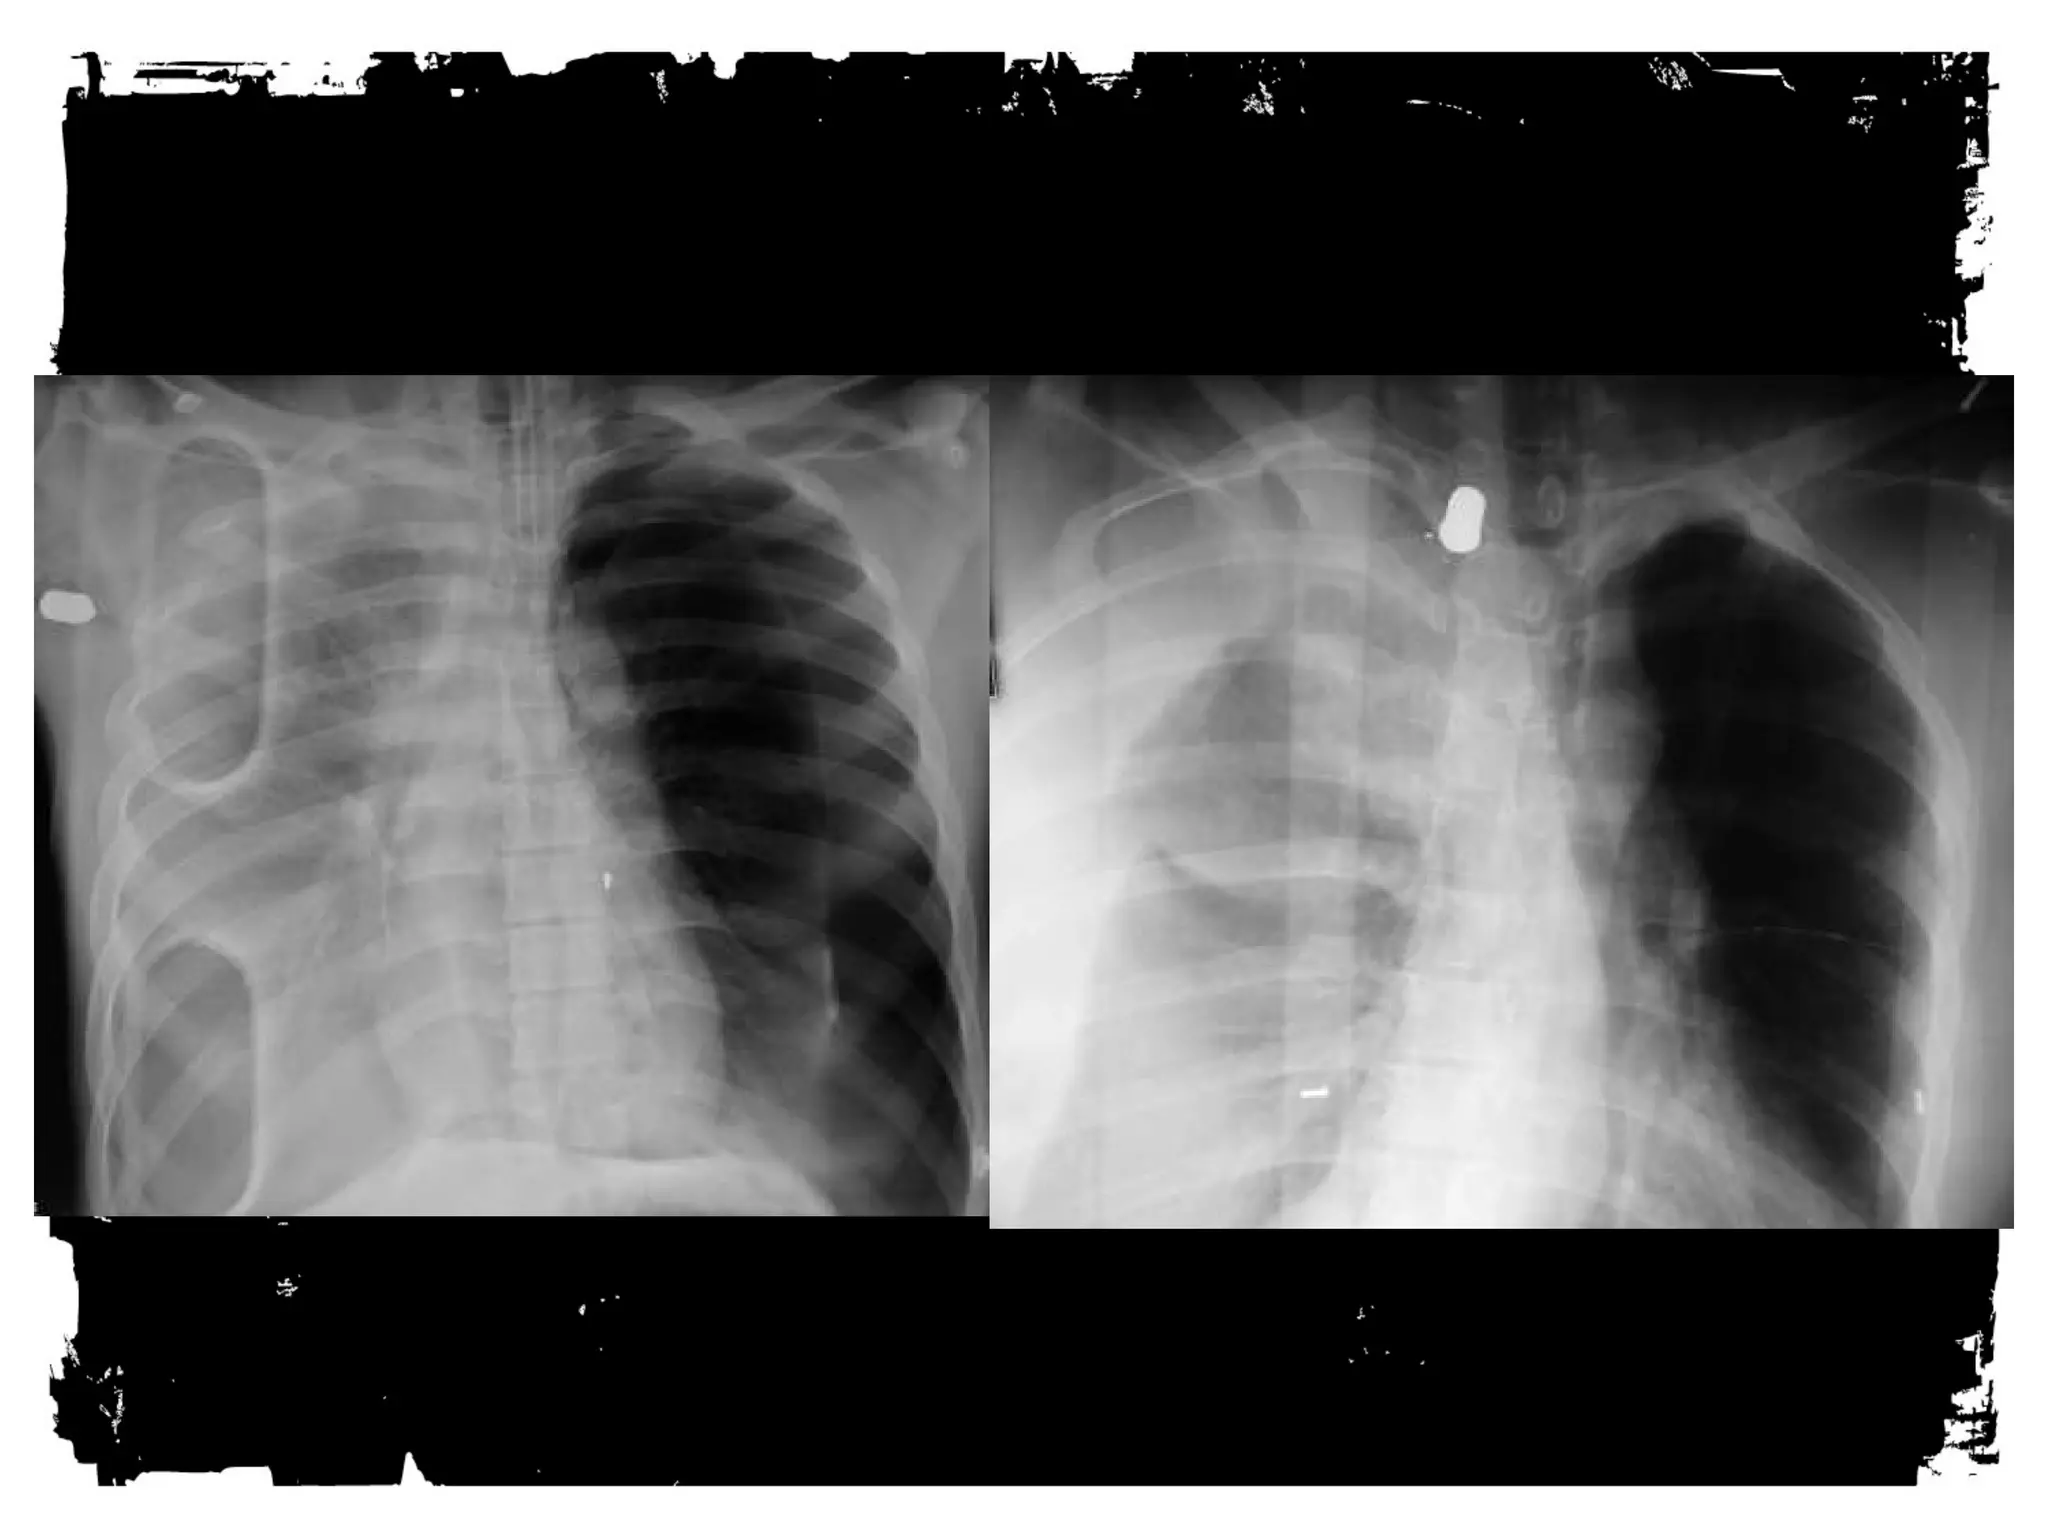

PNEUMOTHORAX: CT

Much more sensitive than plain films. Even a small

traumatic pneumothorax is important, especially if

patient mechanically ventilated or going to OR: A

simple pneumothorax can be converted into a life-threatening

tension pneumothorax.

PNEUMOTHORAX:

Diagnostic limitations of supine view

Supine AP view has limited sensitivity: 50%.

Deep sulcus sign.

Too sharp heart border/hemidiaphragm sign.

Increased lucency over lower chest.

Subpulmonic air sign.

Can see vessels.